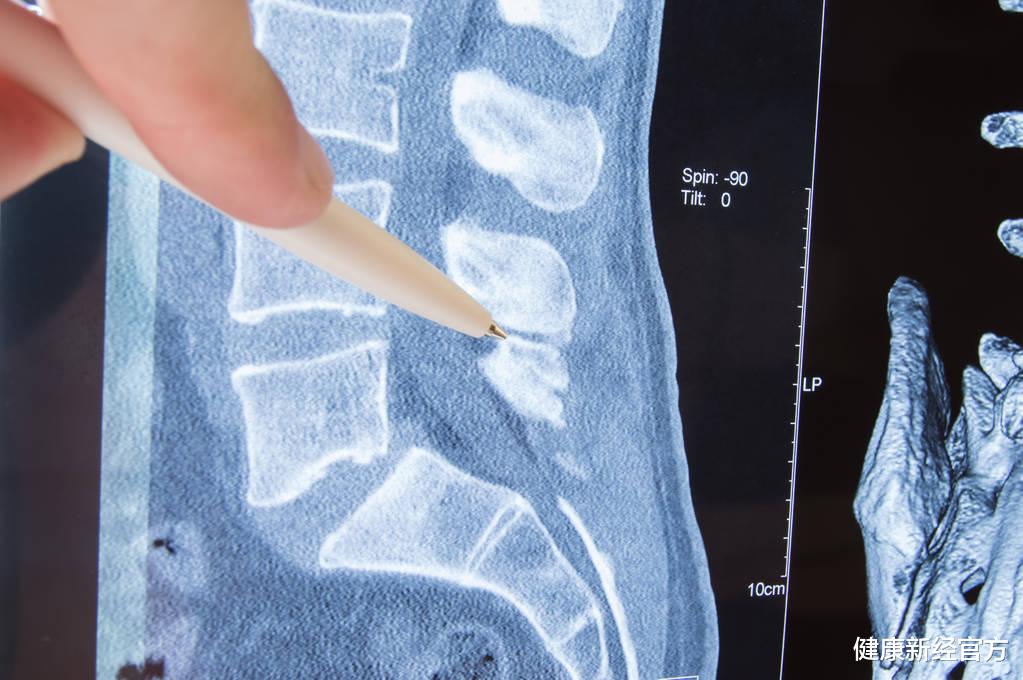

好在他是和他的儿子一起 , 他儿子见状 , 赶紧一把搀扶着他的父亲 , 看着他父亲痛苦的表情 , 就赶紧往医院送去 , 到了医院后 , 经过医生的一番检查 , 显示腰椎骨折 , 需要及时手术处理 。

医生说:这其实是因为你父亲还患有严重的骨质疏松 , 骨密度现在已经低至-2.8 , 所以骨骼中的骨质量已经流逝的比较严重 , 就会因为一点小的磕碰就导致骨骼 , 所以在以后的时间中 , 一定要及时预防 , 不要让骨质疏松在恶化 。